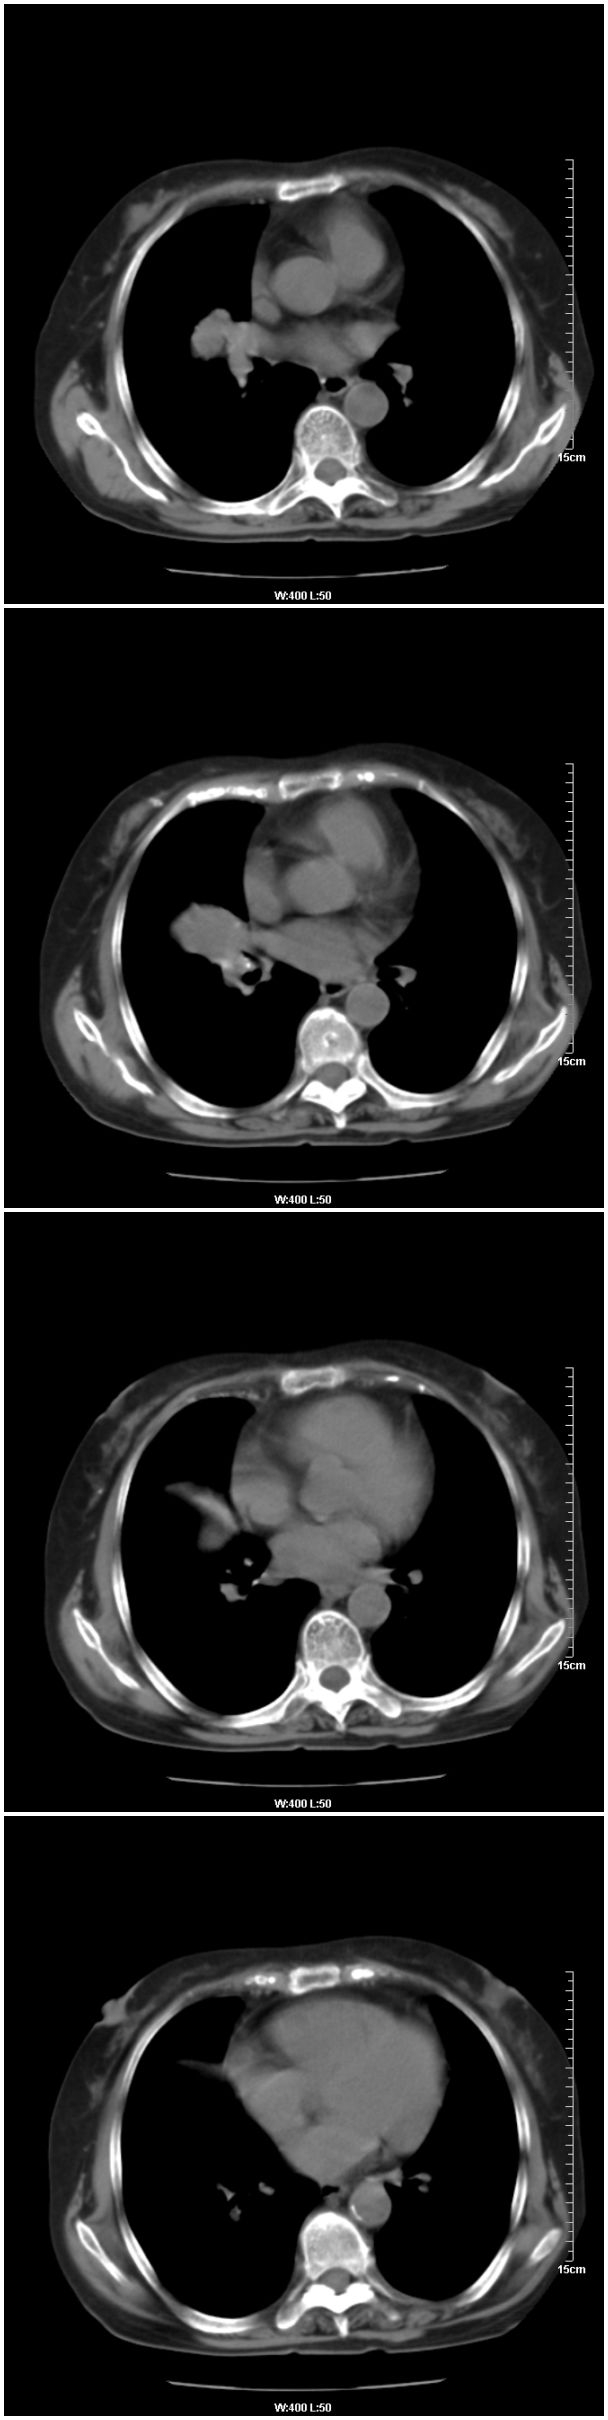

女性,78岁。术前体检发现肺部病变,看看还有什么问题?肺病变是什么性质?

本例临床是以乳腺癌的术前检查平片发现肺部病变的,请战友们看乳腺病变是否能够看出来,在哪一侧?

在右侧,支持!右肺中心型肺癌! 右乳腺肿物。

支持!右肺中叶中心型肺癌!右侧乳腺内上象限结节,建议薄扫

乳腺病在右侧

右侧乳腺占位,右肺门结节状-----肿大淋巴结?

乳腺病变在右侧   是否可考虑为乳腺癌肺部转移

乳腺病变在右侧,右肺门区新生物伴右中叶阻塞性肺炎、部分部张

右肺中叶不规则肿块,管腔阻塞,心包内少量积液,支持右肺中心型肺癌。

应该是右肺中心型肺癌,乳腺的肿物应该在右侧,看见右侧有结节,并乳头凹陷

1.右侧乳腺病变。

2.右肺病变,考虑:肺癌可能性大。(病变边缘光滑,硬化性血管瘤或其他良性肿瘤待除外)

右侧乳腺内上象限结节影,边缘模糊,右肺病变相邻支气管内见软组织密度影及斑点样钙化灶,考虑肺癌可能性大,建议结合纤支镜检查。

右肺中央型肺癌伴中叶肺不张。

右乳腺内结节病灶,如增强扫描动脉期结节呈明显强化可考虑乳癌。